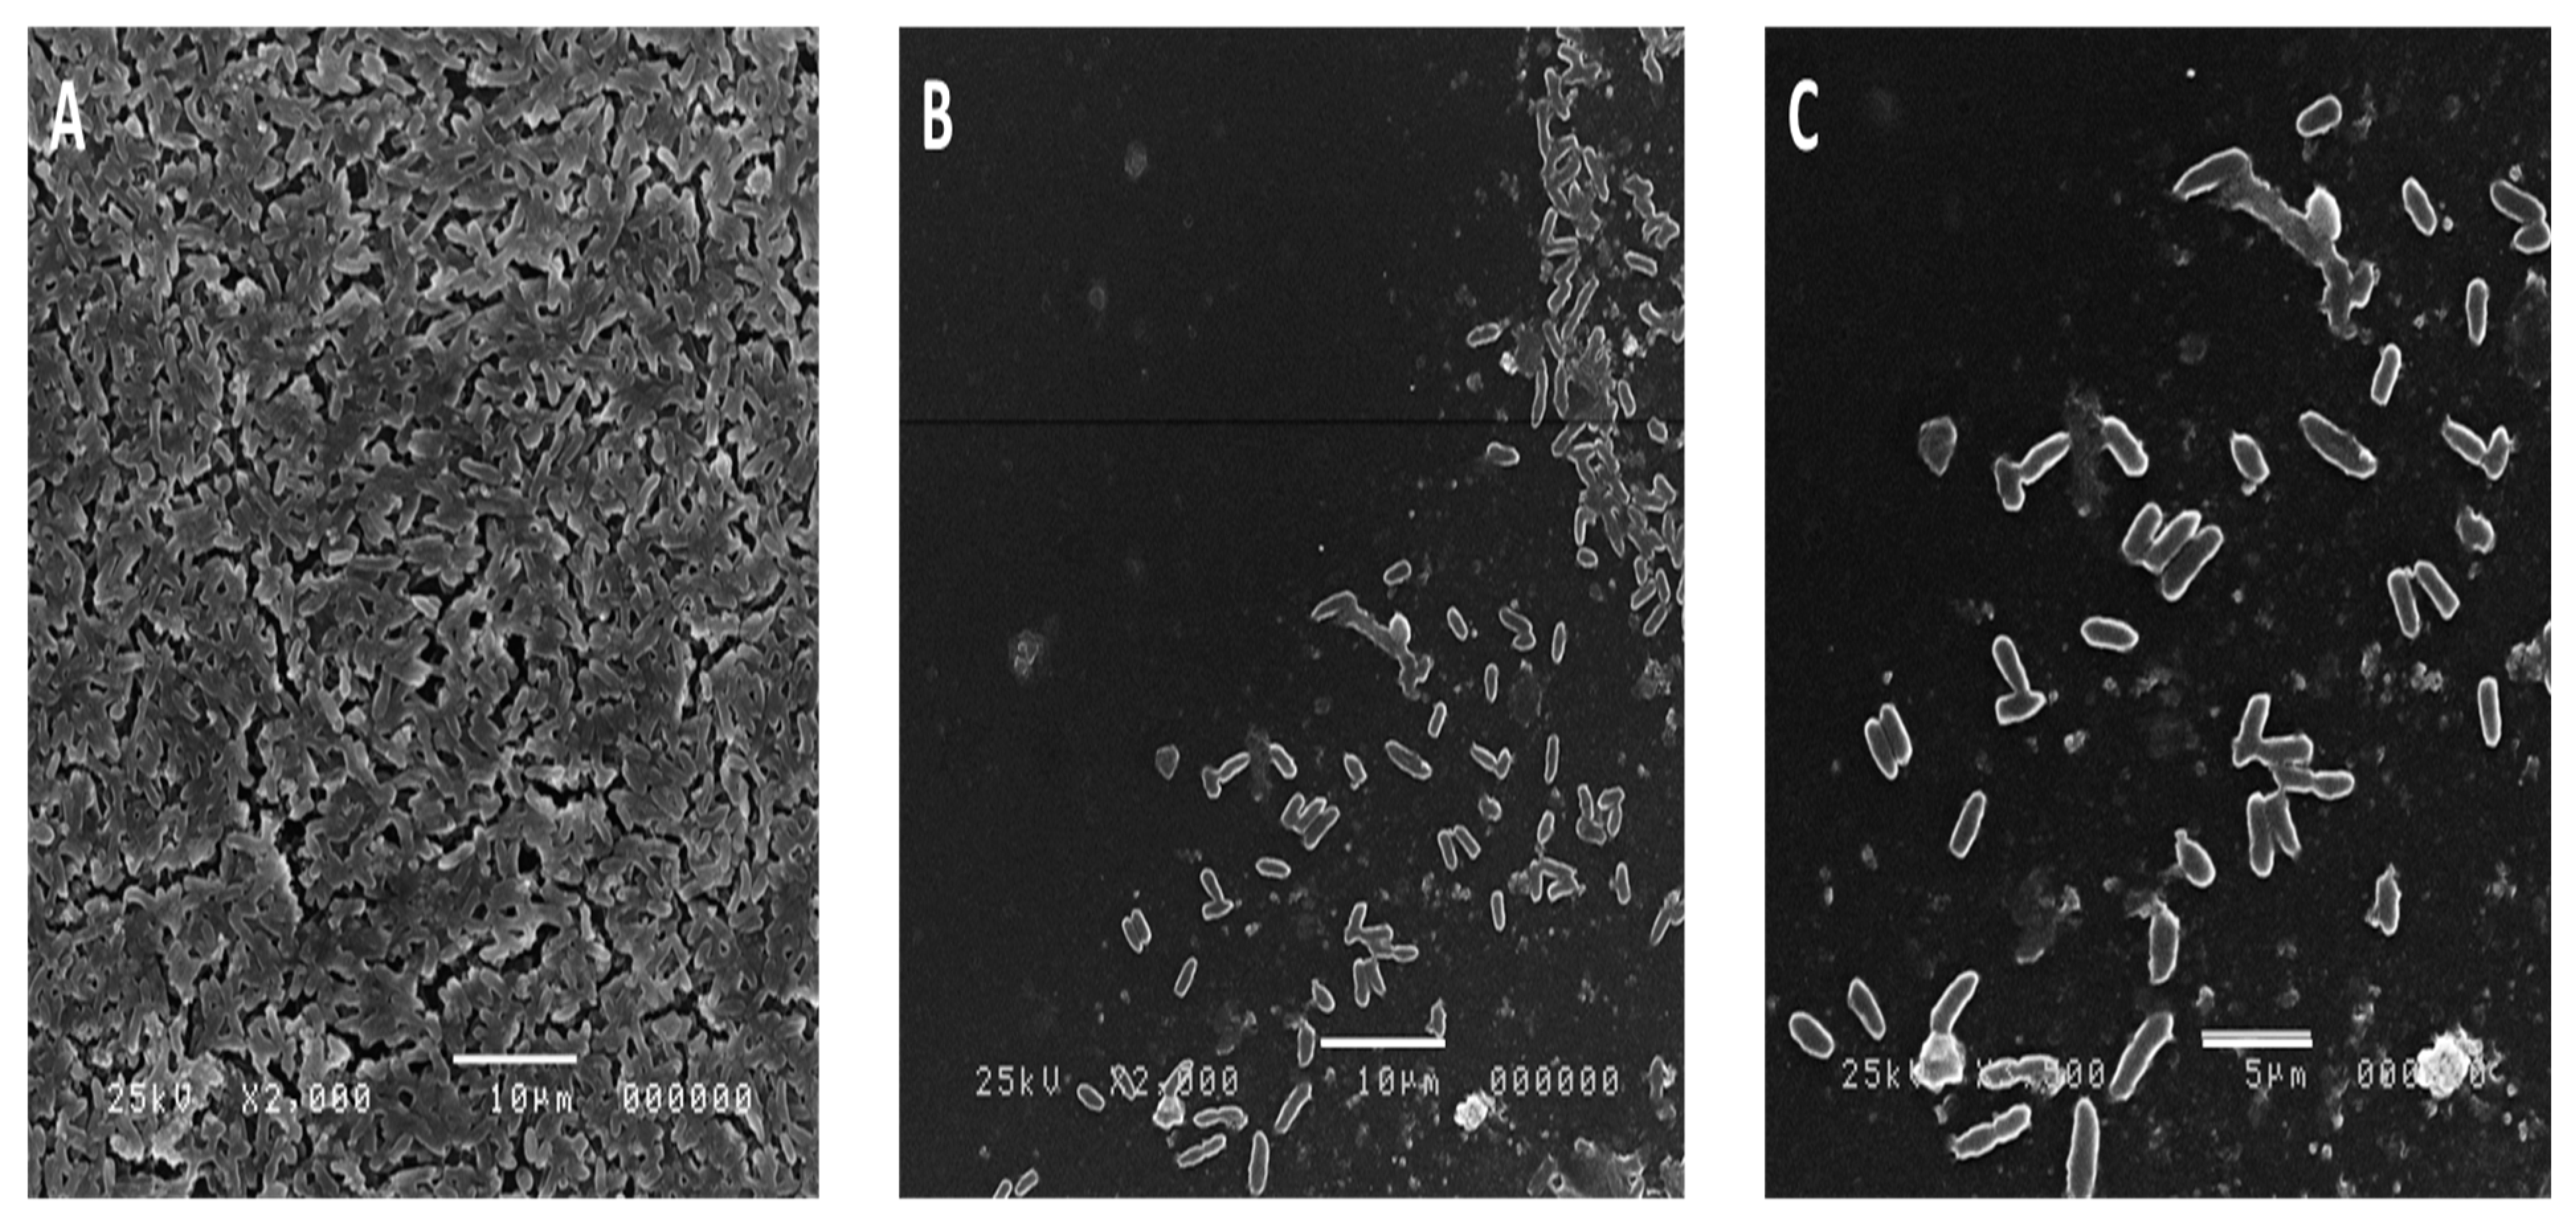

2.8. Effect of the Algal Extract on the Biofilm Architecture of P. aeruginosa Using SEM